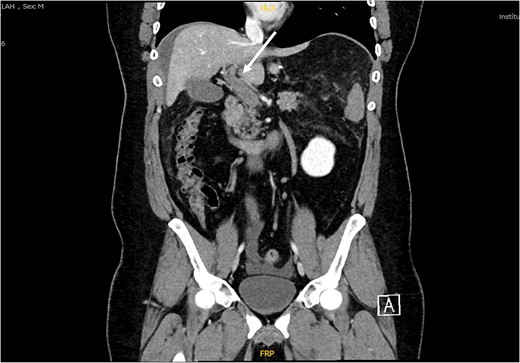

Patient was admitted, and his laboratory investigations demonstrated a normal CBC level, electrolytes were also within normal level, total bilirubin: 17.10 μmol/L, direct bilirubin: 8.80 μmol/L, amino transferase alanine: 36.00 u/L, amino transferase aspartate: 19.00 u/L, alkaline phosphatase: 83 0.00 u/L. Abdomen ultrasound demonstrated mild to moderate intraperitoneal fluid collection, noted mainly in the perihepatic, peri splenic region (Fig. 1). Computed tomography (CT) with oral and IV contrast was ordered for further assessment. The CT showed a non-enhancing portal vein and its branches, a superior mesenteric vein and its tributaries, which are engorged and associated with dirty and congested mesentery, as well as a small amount of peritoneal free fluid denoting venous thrombosis along the portal mesenteric axis with no evidence of contrast leak from the gastric sleeve (Fig. 2). Vascular surgery and hematology consultations were immediately done; they assessed the patient and started him on enoxaparin 100 mg along with a serial abdominal exam. On Day 2 of the current admission, the patient had one episode of fresh blood per rectum, around 150 ml of fresh blood, and dark blood-tinged vomiting of minimal quantity around 10 ml. The patient became agitated, and his abdomen was distended with generalized tenderness. He was immediately resuscitated with two unmatched red blood cell pack transfusions, and then shifted to intensive care units. CT scan angiography of the abdomen was done at that time and reported as follows: non-enhancing portal vein and its branches, superior mesenteric vein and its tributaries, which are engorged and associated with dirty and congested mesentery with a slight increase in the amount of peritoneal free fluid denting venous thrombosis along the portal mesenteric axis. Mild diffuse mural wall thickening of the small bowel is likely related to venous congestion. Aorto-iliac arteries: the visualized abdominal aorta and its bifurcation into right and left common iliac arteries appear intact. The common iliac arteries, internal and external iliac arteries appear intact bilaterally. Mesenteric arteries: the main trunk of the superior mesenteric artery appears intact with no obvious segmental arterial stenosis or occlusion. The inferior mesenteric artery and its main divisions appear intact, with no obvious main or branch occlusion. Celiac artery: The celiac artery and its main divisions, including hepatic, gastric, and splenic divisions, appear intact with no obvious main or branch occlusion.

CT scan abdomen and pelvis, coronal view showing non enhancement of portal vein and its branches indicating venous thrombosis along the portal mesenteric axis (white arrow).